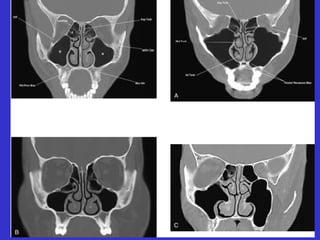

Este documento describe las diferentes proyecciones radiográficas utilizadas para examinar los senos paranasales, incluyendo las proyecciones básicas de Caldwell, Waters lateral y las proyecciones especiales como Hirtz y Waters mentonasal. También describe las diferentes estructuras anatómicas que componen el complejo ostiomeatal anterior y posterior de los senos paranasales.